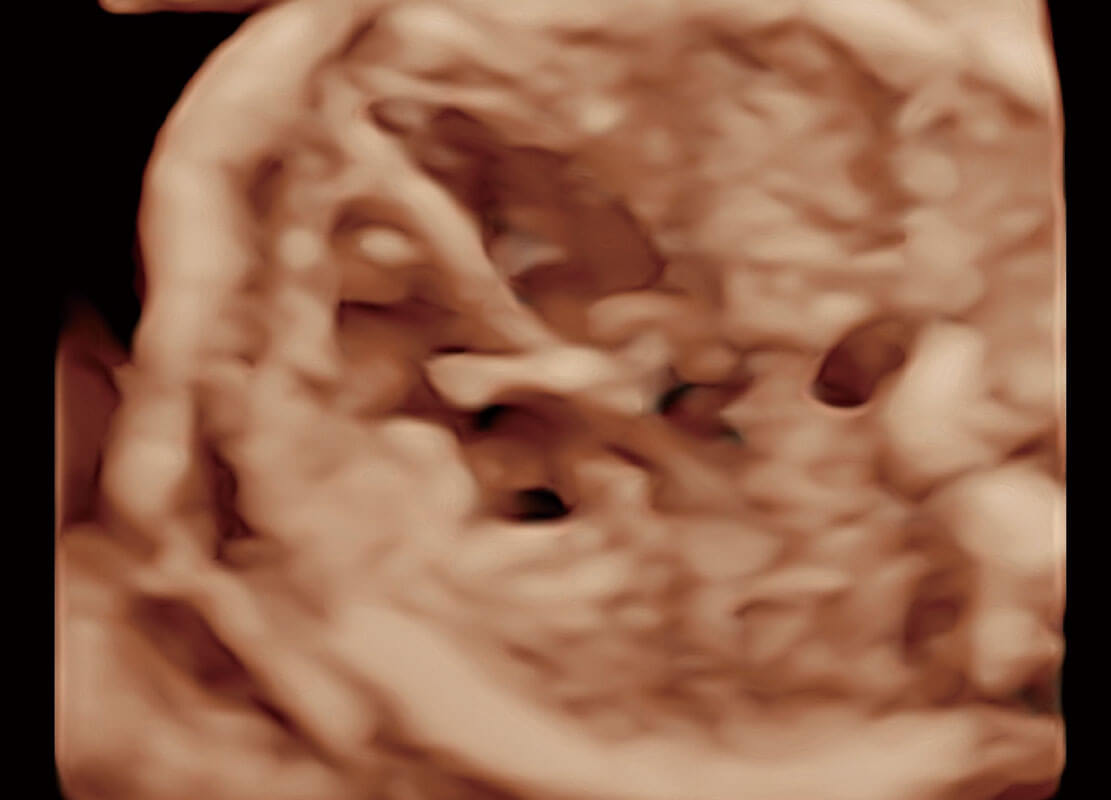

腔内妇科-卵巢

腔内三维-宫内节育器

腔内三维-光影成像